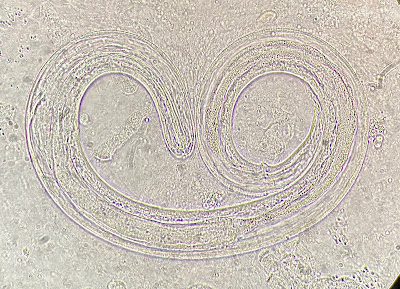

For our last case of May, we have a fun submission from Dr. Megan Shaughnessy. She noted the following in some fresh monkfish she purchased from a small local grocery store. What is the likely identification? Also, what is the risk to humans if ingested?

Answer to the Parasite Case of the Week 684: Anisakid L3 larvae

This is a nematode in the Anisakidae family, likely Pseudoterranova or Anisakis spp., the two most common cause of human anisakiasis, as many of you suggested. A third genus, Contracaecum, is also a possibility. Mario George Nascimento and Melinh Luong point out that its dark color implicates Pseudoterranova (vs Anasakis which is usually white/pink/red).

However definitive identification to the genus level requires closer inspection of the intestinal cecum and its positioning as mentioned by Idzi P. in the comments and seen in Case 563 which he donated.